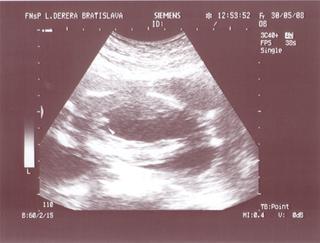

@lucy56 morfoligicky utz je zameraný na hodnotenie správnosti vývoja jednotlivých orgánov plodu a zároveň sa odmeraním určitých parametrov hodnotí aj správnosť rastu dieťaťa. nebudes tak dobre vidiet dietatko ako na 3D. 3D utz :Moderný 3D ultrazvuk umožňuje vidieť pohyby Vášho bábätka, ako na filmovom plátne. Pohľad do tváre pôsobí na budúcu mamičku ukľudňujúco. Prepočítajme spolu prstíky a presvedčme sa, že je všetko v poriadku.Celé vyšetrenie je možné uchovávať na DVD nosiči.Najvhodnejší je záznam v 22-26. týždni tehotenstva.